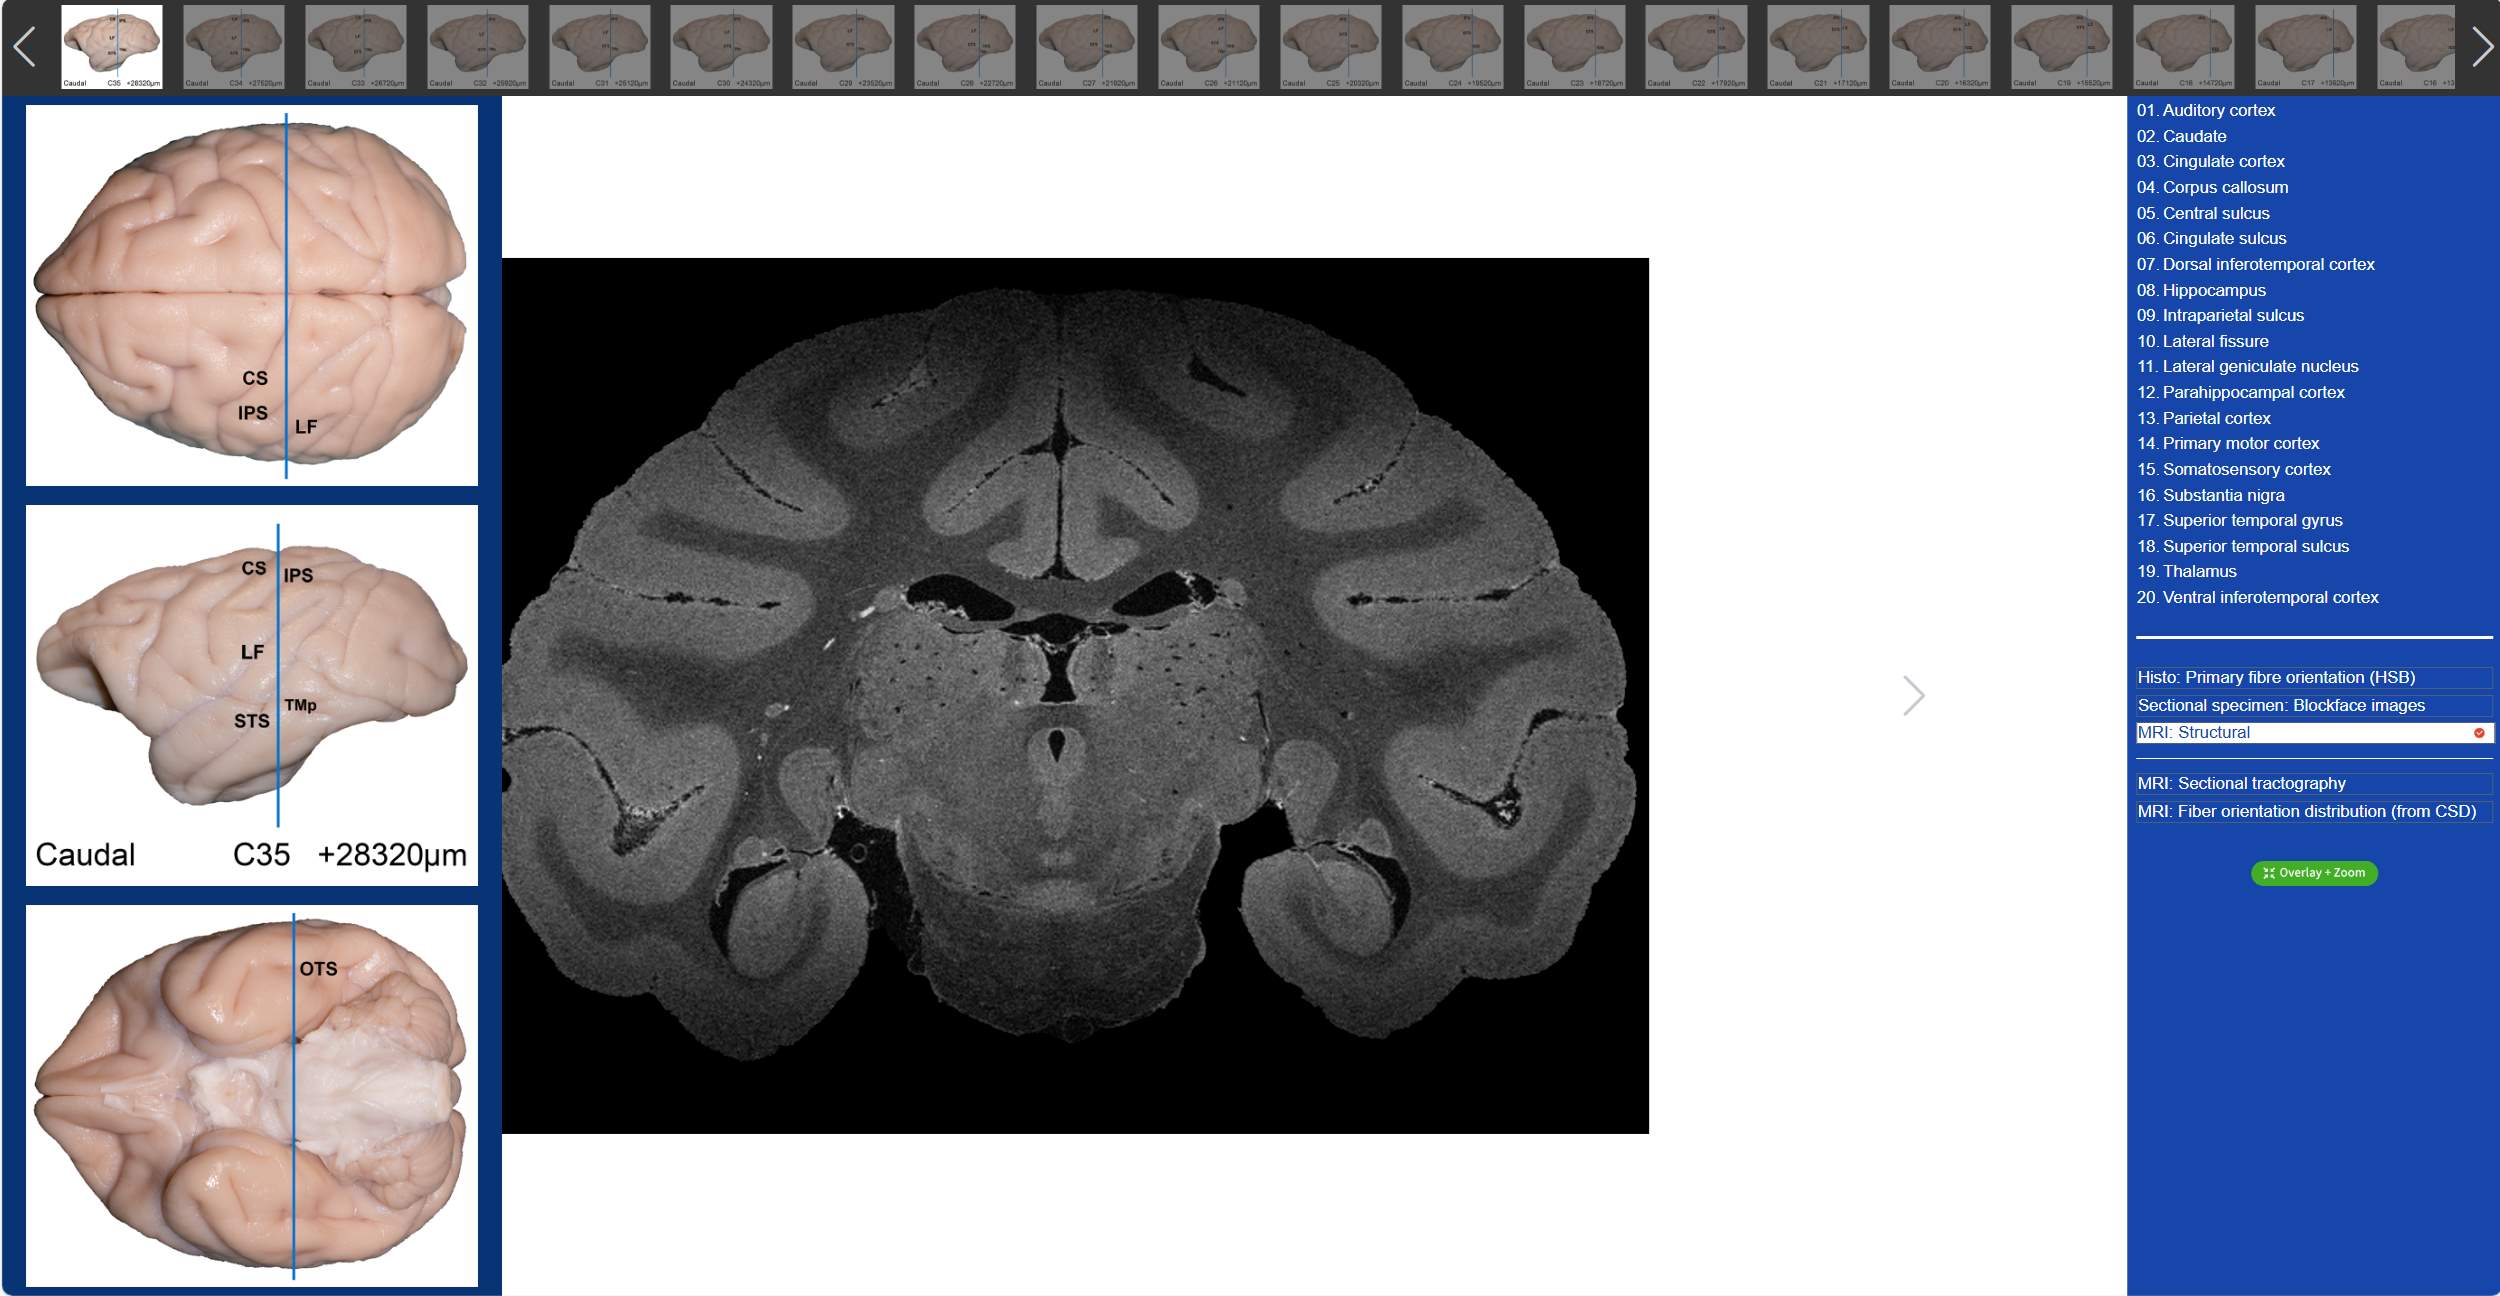

值得一提的是,在“动物脑乐园”里,不仅可以观察到猕猴3D脑标本,还可以看到猕猴的全脑切片。吴劲松教授团队从同一猴脑的离体MRI及全脑组织切片髓鞘染色(LFB)数据集中,间隔800μm取一层,构建了集合组织切片髓鞘染色(LFB)、组织切片髓鞘染色-伪彩化、断层标本图、高分辨率MRI结构像及离体脑dMRI断层纤维束成像和纤维方向分布图(限制球面反卷积-CSD)六大模态的断层对照图谱。我们只需要点击相应的解剖名称,就可以在图谱上对应位置显示标记,同时可与另外两大模态的dMRI方向性信息进行对照,极大的方便了我们的观看。